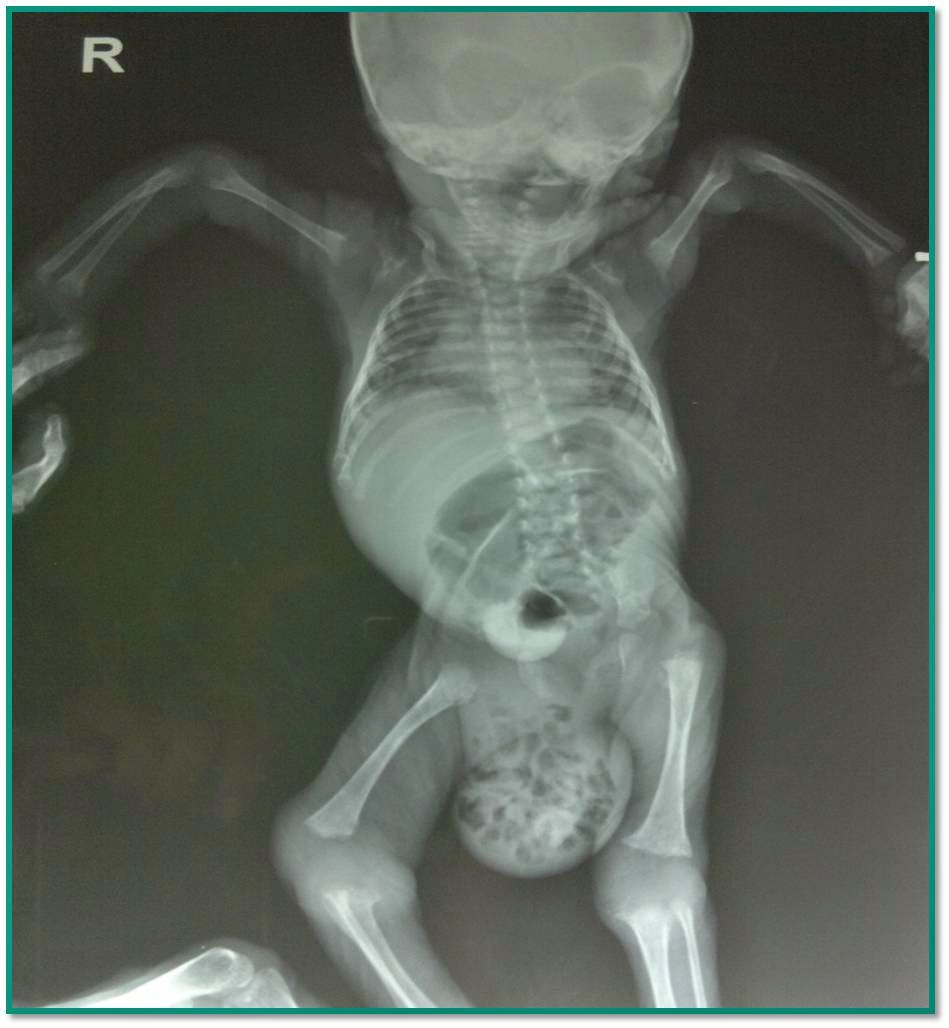

Фото Грыжи Яйца

Фото Грыжи Яйца 111 фотографий